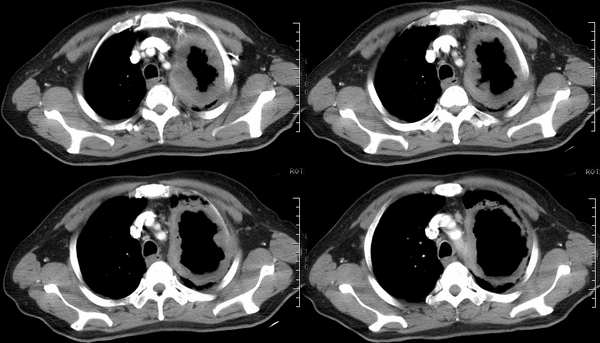

ct2533:张巍 提供 患男,24岁,胸痛数月.

穿刺活检为干酪坏死物.胸壁结核瘤!

ct1240:song7715

病人24岁,身体偏瘦,半月前曾有高烧,现无阳性体征,血项不高。透视时无意发现。

右肺结节病理结果:结核球http://www.radida.com/radinet/read.php?tid=3611

ct1585:liuwensi 提供

m,64y,体检发现右肺上叶后段孤立性结节,纵隔内未见肿大淋巴结影右肺病理是结核球